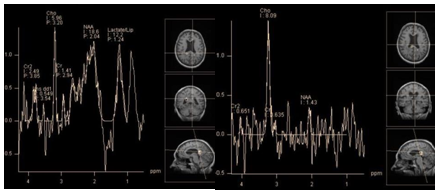

The metabolite profile of hemangiopericytoma, like of the most other extra axial tumors shows high levels of choline, creatine and lack of N-acetylaspartate. Unlike meningiomas, the level of the glutamine/glutamate complex is not high, alanine is not recognized, a "distinct peak" at 3.8 ppm is absent. Instead, hemangiopericytomas show high peaks at 3.56 ppm, and 3.4 ppm, attributed to myo-inositol/glycine, and glucose, respectively, by some authors.30,31 However, according to Young-Dae Cho et al.,32 these peaks should be classified as resonant frequencies of the "unknown molecule" because; in contrast to myo-inositol and glucose (that have T2 within 110 ms) both of these peaks are observed at long TE.32 However, it is not clear, why glycine, which has the same resonant frequency as myo-inositol (3.56 ppm), and long T2, was not mentioned by the authors (Figure 12).

Figure 12 Hemangiopericytoma. PRESS TE 30 ms (a), PRESS TE 135 ms (b). The dominant lipid peak at 1.3 ppm is seen on both short and intermediate TE, without changing phase (a,b). Also peak of "unknown molecule" / glycine (?) At 3.56 ppm clearly seen on spectra obtained with both TEs.

Choroid plexus papilloma and choroid plexus carcinoma are rare neuroepithelial tumors. Accordingly, there is little data in literature on their metabolic profiles. They should be differentiated from other tumors of this localization, especially with meningiomas, as well as oligodendrogliomas and central neurocytomas. Papilloma, as carcinoma show two dominant peaks: myo-inositol and choline. Ratio of choline and myo-inositol corresponds to the degree of malignancy: namely choline levels are higher in carcinomas. In addition, carcinoma may contain lactate. Peaks of creatine and N-acetylaspartate is absent in choroid plexus tumors. Metastases account for about 50% of all intracranial tumors. Solitary metastases first of all, should be differentiated with glioblastomas. But some of them, of superficial or meningeal localization, have the same radiological features as meningiomas. In this case spectroscopy plays an important role in differential diagnosis. The metabolite profile of metastases is characterized by two dominant peaks: choline and lipids at 1.3 ppm. Lipids in metastases of certain origin (lung cancer, etc.) can have long T2. Thus, the spectra obtained with TE 135 ms may show a positive peak at 1.3 ppm, instead of the inverted lactate doublet (Figure 13). Multiplets of the glutamine/glutamate complex are also sometimes observed, but not dominant as in meningiomas. Alanine and its "distinct peak" at 3.8 ppm are absent. The level of creatine is low, peak NAA, as in other extra axial tumors is missing.32 Metabolic profiles of metastases and glioblastoma have much in common33 but according to some authors, there are some differences19,34 which will be covered in more detail in the discussion of the differential diagnosis of Intra axial tumors.

Figure 13 Meningeal metastasis. PRESS TE 30 ms (a), PRESS TE 135 ms (b). The dominant lipid peak at 1.3 ppm is seen on both short and intermediate TE, without changing phase (a,b). Relatively high peaks Glx (a). Choline peak seems insignificant compared with the peak of lipids (a).